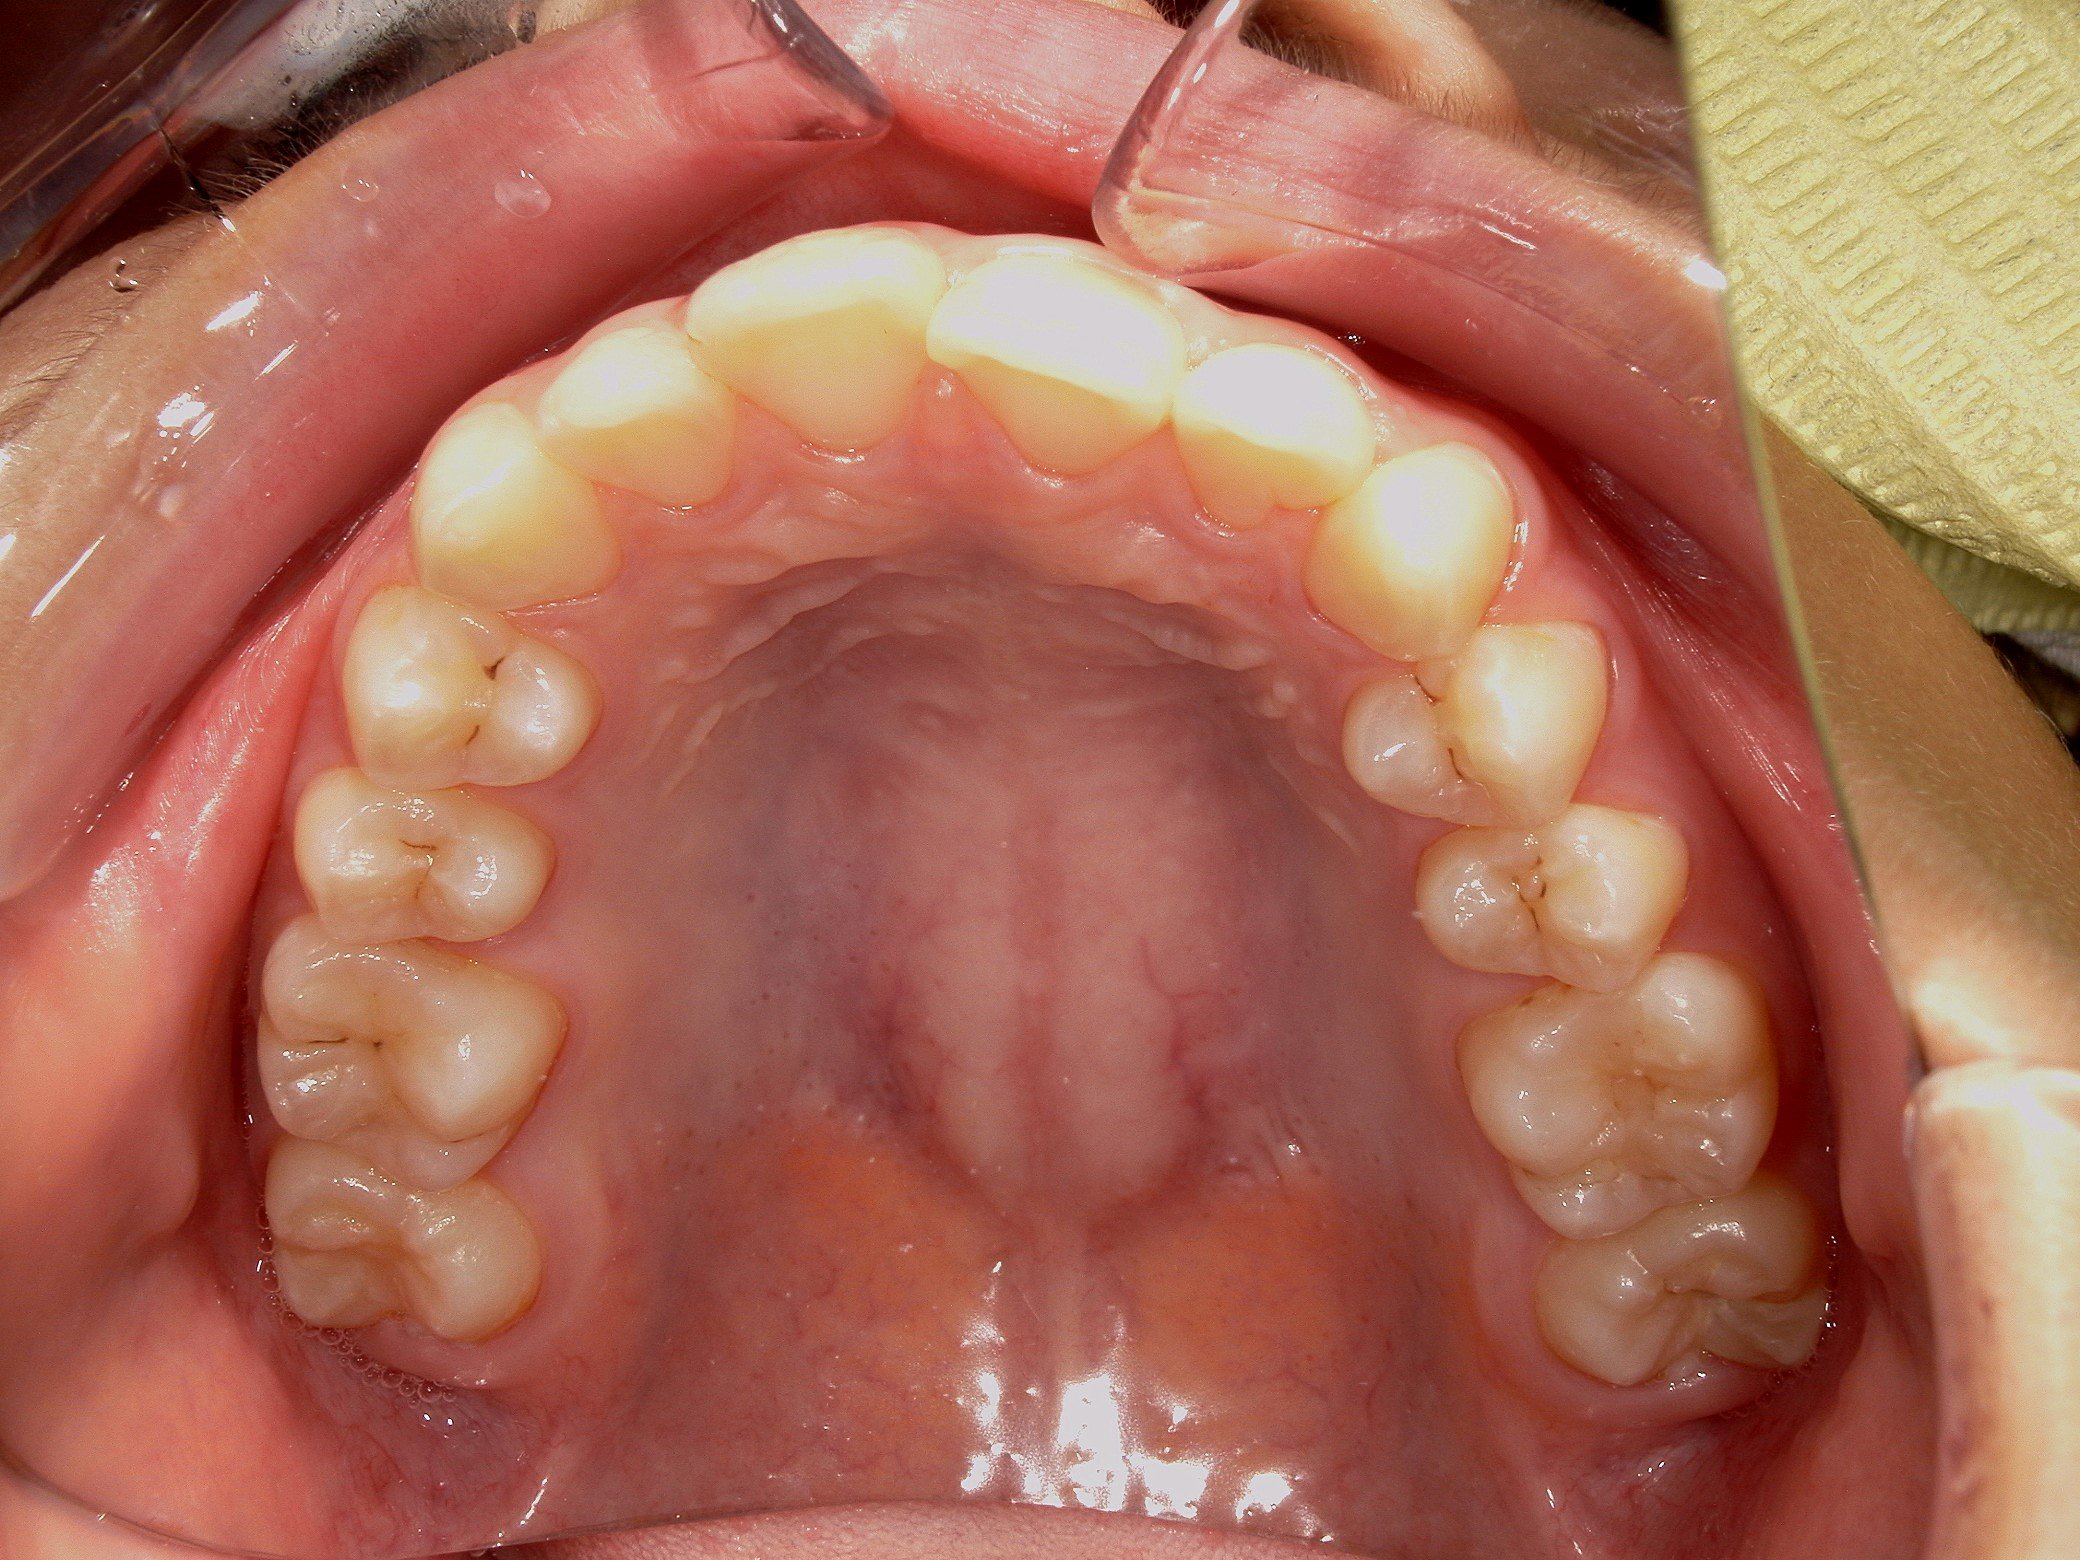

大きな問題点: 本来なら生えきっているはずの下顎左右の第二大臼歯(一番奥の7番目の歯)が、萌出時期を過ぎても歯ぐきに埋まったままの「半萌出状態」となっていました。

上顎は左右の4番、下顎は左右の5番を抜歯する計画としました。

・スペース不足で生えてこなかった下顎の7番も、正常な位置へと誘導することができました。